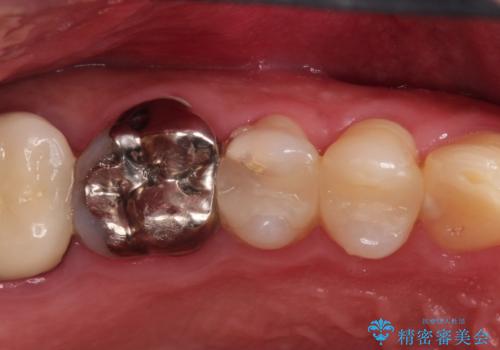

- 定期検診にて不良補綴物、及び虫歯を認めオールセラミッククラウンにて治療を行いました。

右上第二小臼歯はカリエス除去中に露髄を認め、部分的断髄法にて歯髄を保存しております。